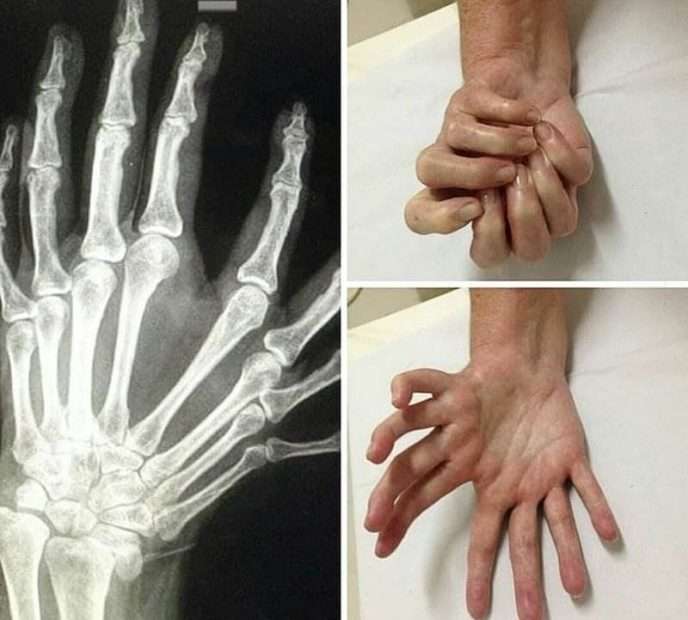

Այս լուսանկարները կարող են ապշեցնել յուրաքանչյուրին։ Արդյո՞ք սա ֆոտոշոփ է։ Ահա թե այս լուսանկարներից որոնք են իրական, իսկ որոնք են ֆոտոշոփի մասնագետի աշխատանք։